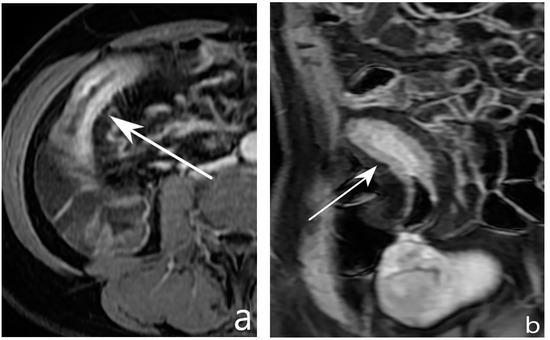

5.2. Fibro-Stenotic Subtype